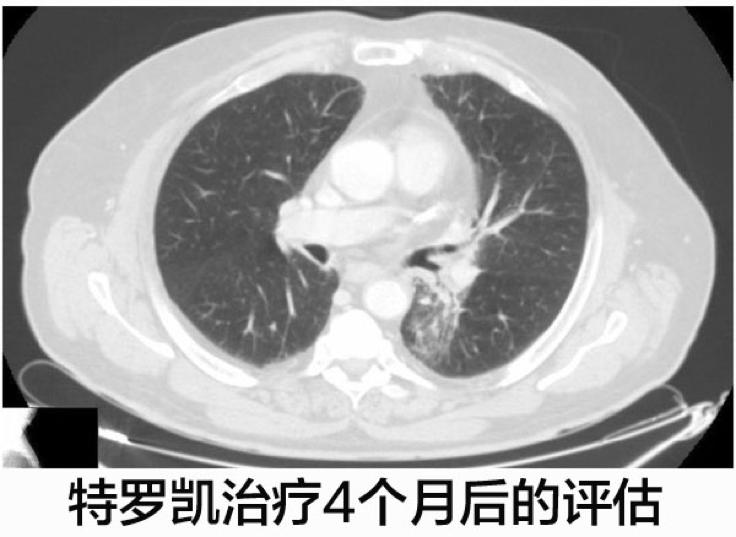

这名病人开始了厄洛替尼(特罗凯)的二线治疗,每天的计量是150mg,特罗凯治疗4个月之后CT显示肺部病灶体积减少。